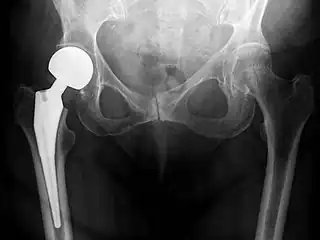

Cement-free implant sixteen days after surgery. Femoral component is cobalt chromium combined with titanium which induces bone growth into the implant. Ceramic head. Acetabular cup coated with bone growth-inducing material and held temporarily in place with a single screw.